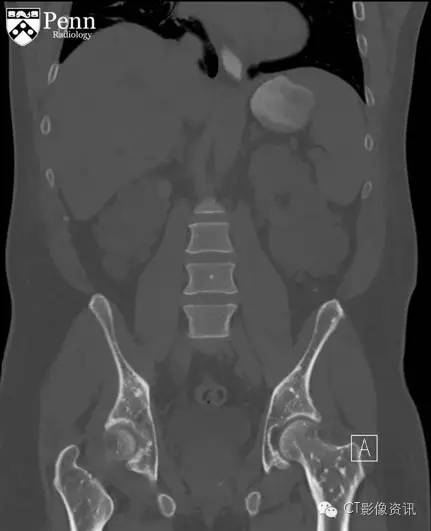

腹盆部冠状位以及轴位CT影像骨窗显示多个边界清晰的细小硬化灶呈现圆形、卵圆形以及线样;其直径从几毫米到一厘米不等,分布在股骨以及髋臼顶部;不伴有骨膜反应和骨质破坏。在软组织窗冠状位CT图像显示双侧肾影增大,伴随大量囊样密度影;此外在肝脏也可见囊样密度;可能为常染色体显性遗传多囊肾后遗症导致。

最终诊断:骨斑点症